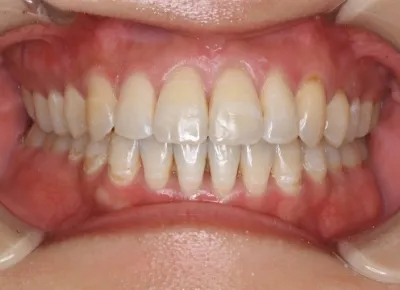

Before

After

治療期間

費用総額